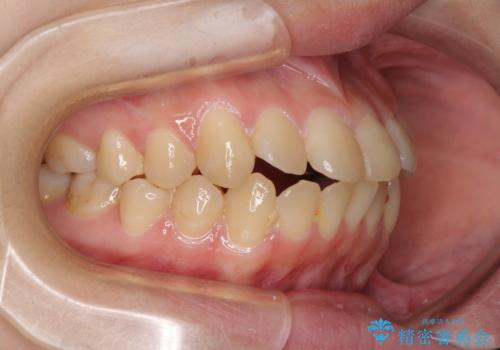

- 上下前歯が前方に飛び出しているとのことで来院された患者様です。

上下左右第一小臼歯4本を抜歯して、積極的に口元を引っ込めるよう、ワイヤー装置にて矯正治療を行うこととしました。

口元の突出感は著しく改善され、横顔の印象が大きく変化しました。